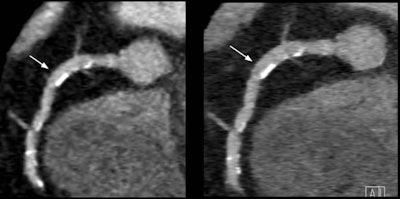

"With filtered back projection and the conventional detector at the 60% stenosis, it seems like it almost no lumen left, but when you go to the integrated detector you can see the effect, which becomes really apparent when you look at the combination of the thinner slice thickness, iterative reconstruction, and the new detector, where you can still discern the lumen at 60% stenosis," he said, and the difference is also visibly apparent at the 50% stenosis level.